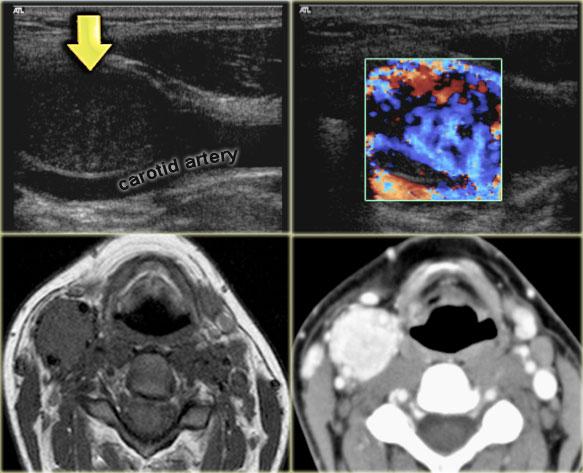

Paraganglioma: Siêu âm Doppler màu, MRI chuỗi xung T1W không tiêm thuốc tương phản từ và CT có tiêm thuốc cản quang

Paraganglioma (2)

Bên trái là hình ảnh của một bệnh nhân nữ 21 tuổi có khối ở bên phải.

Tổn thương này nằm giữa động mạch cảnh trong và động mạch cảnh ngoài, do đó là một khối u thần kinh.

Chẩn đoán phân biệt được giới hạn ở các khối u xuất phát từ dây thần kinh phế vị và đám rối giao cảm.

Trên CT và siêu âm Doppler màu, khối rõ ràng có tăng sinh mạch máu và chẩn đoán duy nhất có thể là paraganglioma.